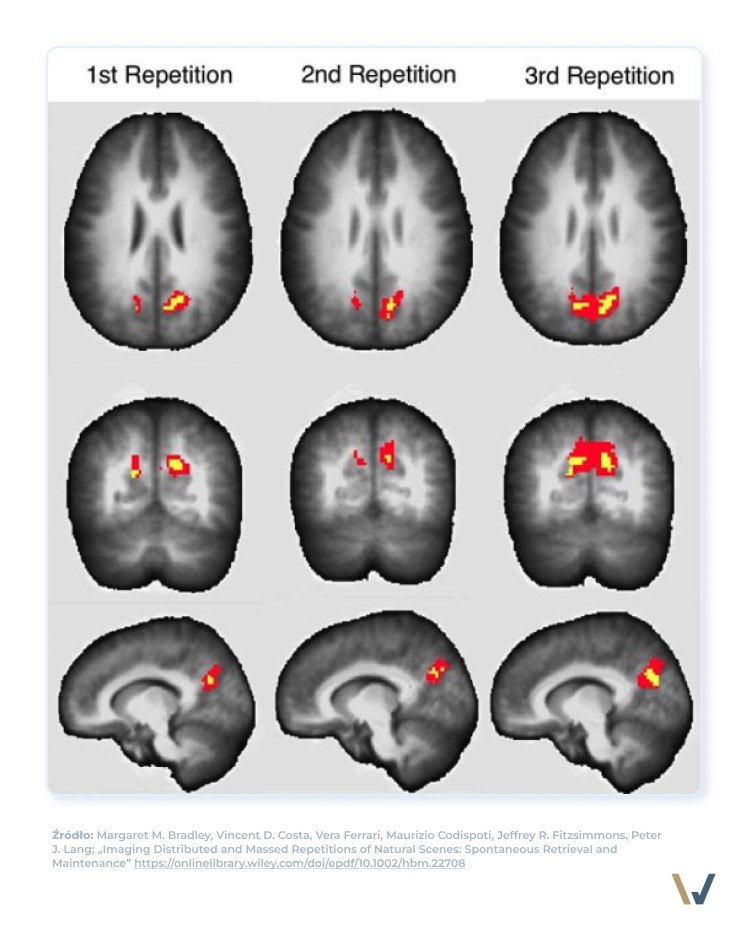

Badania z użyciem fMRI (funkcjonalnego rezonansu magnetycznego) pokazują, że upychanie całej nauki w jednej sesji zmniejsza aktywność mózgu, którą wzbudzają nowe informacje z tego zagadnienia.

👉 Rozłożenie nauki w czasie za to wzmaga aktywność mózgu, ponieważ nie możemy wydobyć informacji z pamięci roboczej, co oznacza, że trudniej nam sobie je przypomnieć. Jednak! Oznacza to również, że lepiej je zapamiętamy.

Jak podsumowuje swoje badania zespół M. M. Bradley rozproszone powtarzanie skłania mózg do odzyskiwania wcześniejszych informacji z pamięci, podczas gdy masowe powtarzanie skłania mózg do krótkotrwałego utrzymania informacji w pamięci krótkotrwałej.